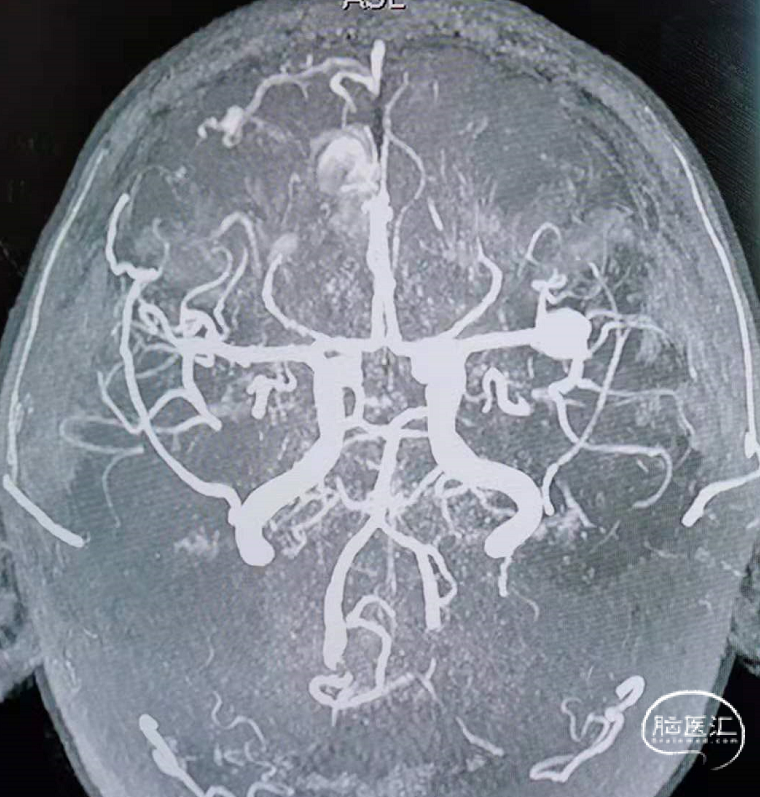

治疗经过